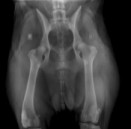

Badaniem można stwierdzić bolesność podczas biernych ruchów w stawie, mniejszy zakres ruchu w stawie, fenomen Ortolaniego – charakterystyczne „klikniecie” w stawie biodrowym wynikające z jego niestabilności. Najdokładniejszym badaniem jest badanie radiologiczne stawów biodrowych. Zdjęcie wykonuję się w projekcji grzbietowo-brzusznej – V-D, pies leży na grzbiecie (niekiedy konieczne jest wykonanie dodatkowych zdjęć w innych projekcjach). W większości przypadków do wykonania takiego zdjęcia konieczne jest uspokojenie pacjenta – sedacja i rozluźnienie mięśni – miorelaksacja, co uzyskuję się za pomocą iniekcyjnych środków farmakologicznych.

Objawy radiologiczne są różne w zależności od stopnia nasilenia zmian w stawie, dotyczyć mogą panewki stawu biodrowego, główki kości udowej lub obu struktur jednocześnie.

Do określenia stopnia dysplazji stosuje się następującą skalę ocen:

A - stawy biodrowe normalne

B - Stawy biodrowe prawie normalne

C - dysplazja nieznaczna

D - dysplazja częściowa (ograniczona)

E - dysplazja ciężka